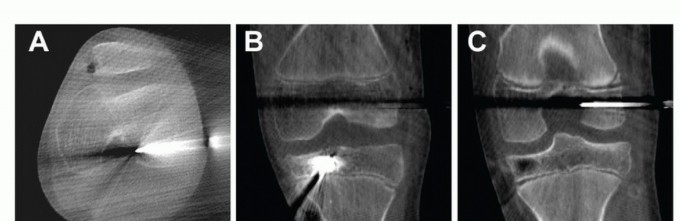

Epiphyseal Tunnel Position Confirmation

Imaging is used to confirm the position of the guidewires and their distance from the physis.

The undulating nature of the distal femoral physis makes accurate assessment of pin placement on plain imaging challenging.

A low-dose, limited-cut CT scan may be performed with an O-arm (Medtronic, Inc., Minneapolis, MN) to provide accurate three-dimensional assessment of pin placement relative to the physis (

TECH FIG 5

).

Alternatively, AP and lateral fluoroscopy can also be used, but again, the undulating nature of the femoral physis can make interpretation challenging.

The position of the femoral guide pin and the depth of the tibial RetroDrill are adjusted accordingly.

TECH FIG 5 • Intraoperative images from a limited-cut CT scan with the femoral guide pin in the epiphysis and the engaged cutting blade and its guide pin seated at the most distal aspect of the tibia tunnel.

*